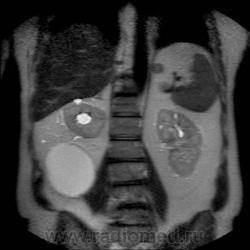

Кистозно-солидное образование н/3 правой почки, солидный компонент хоть и минимальный, но он есть, следует с ним внимательнее разобраться, я бы отнес данное кистозное образование к IV категории по Босняку.

А. эта опухоль больше похожа на "добро" или "зло"?

Добрый вечер. Босняк 4 означает что образование надо рассматривать как злокачественное, пока не будет доказано обратное или подтверждена злокачественная природа.

Сто процентный рак. Без всяких босняков.

Я бы в диф ряде рассмотрел бы эхинококкоз - в нижнем полюсе образования есть перегородка.

А вот метастазов рака почки, по видимому, не видит никто) а они есть)

Пока нет данных морфологии по этой кисте - не отказываюсь от своего мнения об эхинококке. Статьи по изолированому эхинококку почек(всего 3 процента по статистике) и других редких локализаций можно посмотреть здесь http://ifolder.ru/21262829, если кому-то еще интересна дискуссия